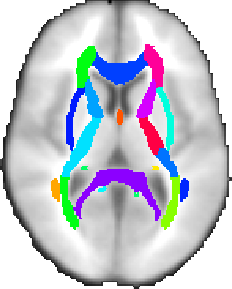

JHU DTI-based white-matter atlases

There are two white-matter atlases, both kindly provided by Dr. Susumu Mori, Laboratory of Brain Anatomical MRI, Johns Hopkins University:

There are two white-matter atlases, both kindly provided by Dr. Susumu Mori, Laboratory of Brain Anatomical MRI, Johns Hopkins University:

In the ICBM-DTI-81 white-matter labels atlas, 48 white matter tract labels were created by hand segmentation of a standard-space average of diffusion MRI tensor maps from 81 subjects; mean age 39 (18:59), M:42, F: 39. The diffusion data was kindly provided by the ICBM DTI workgroup.

In the JHU white-matter tractography atlas, 20 structures were identified probabilistically by averaging the results of running deterministic tractography on 28 normal subjects (mean age 29, M:17, F:11).